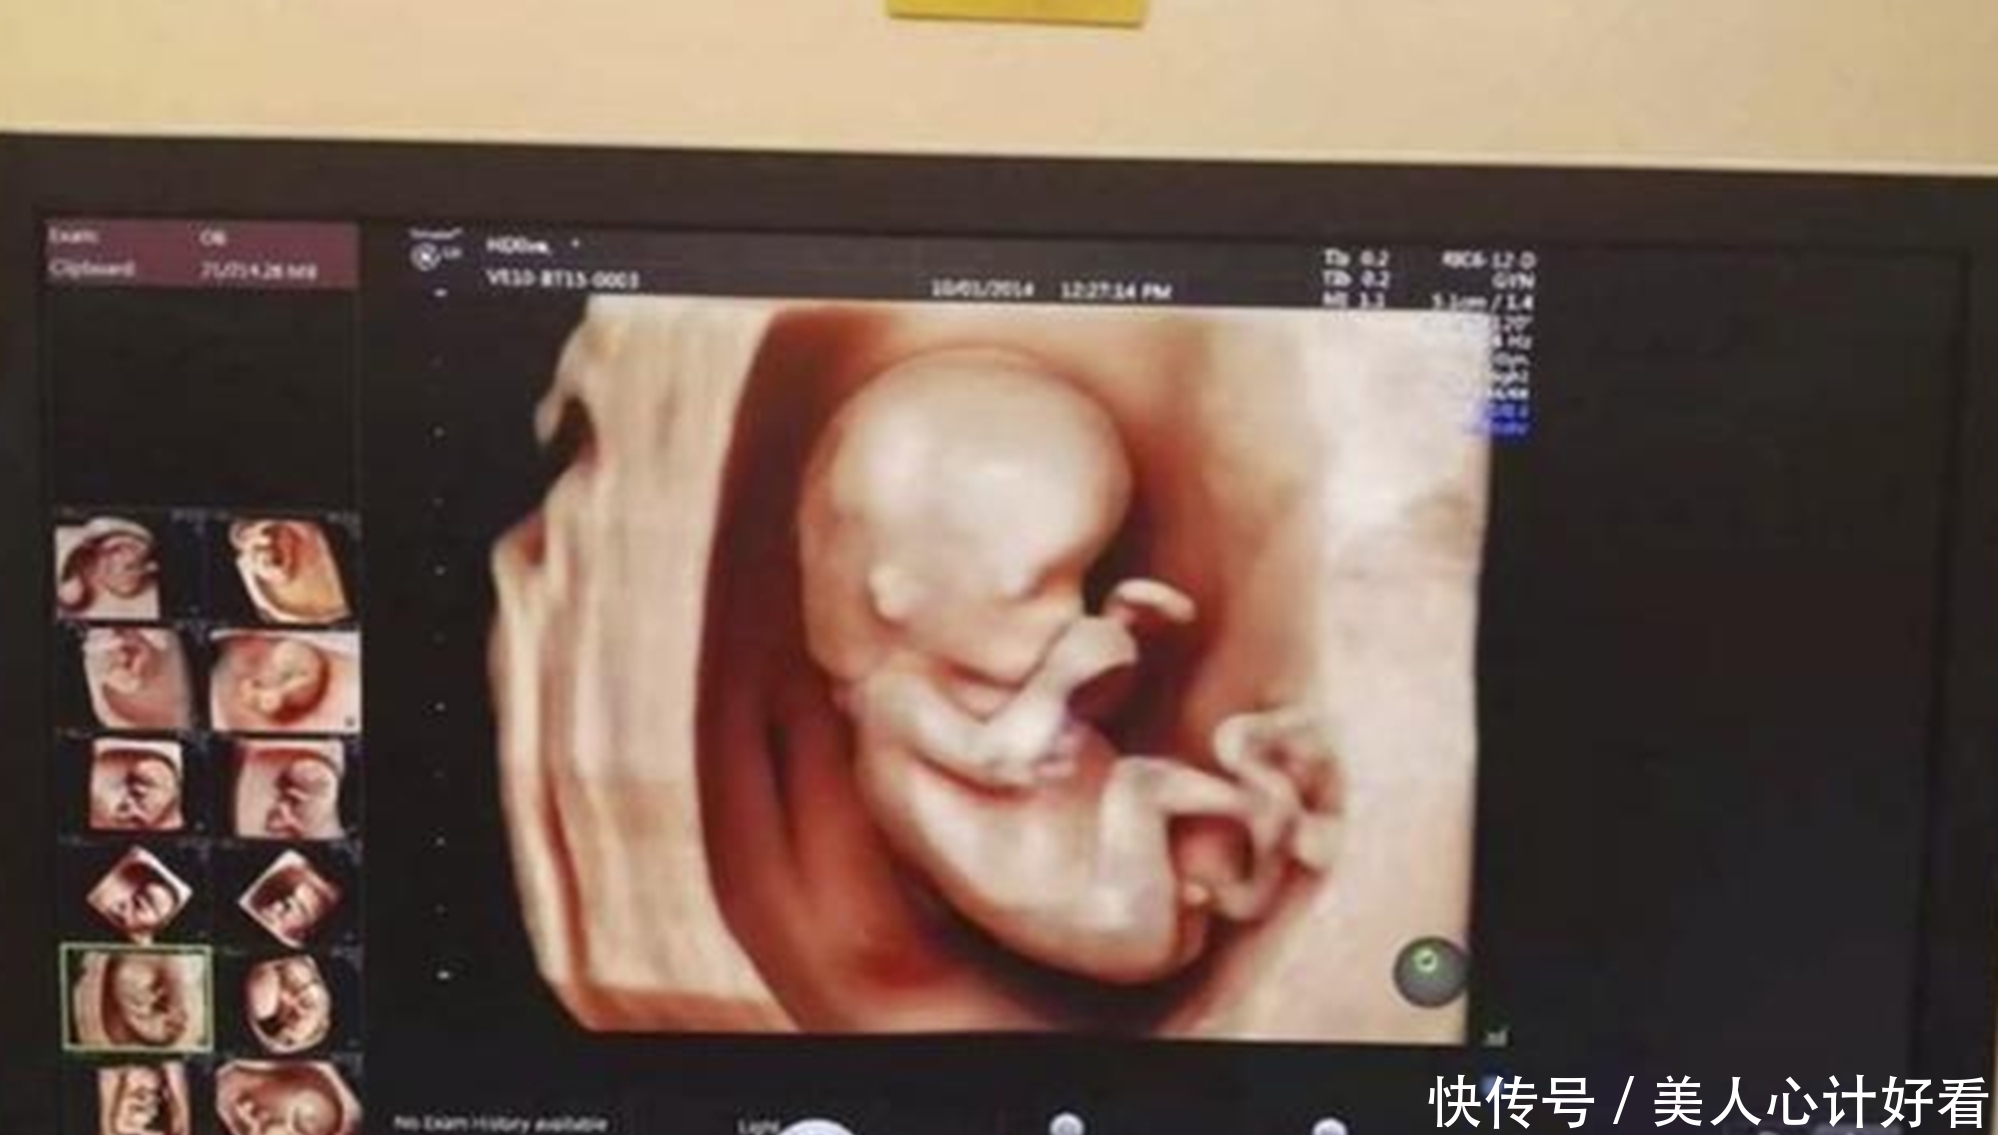

第三次B超是孕妈进入孕晚期的第一次检查,很多人选择四维彩超。

30周的胎儿基本已经成型,妈妈们迫不及待的选择四维彩超,便于更加清晰地看清宝宝的模样。

这次检查也是对胎儿身体的最后一次“排畸”,时间可能会较长,医生检查的也会更加仔细,宝妈也可以在这个时候选择为宝宝“留照合影”。